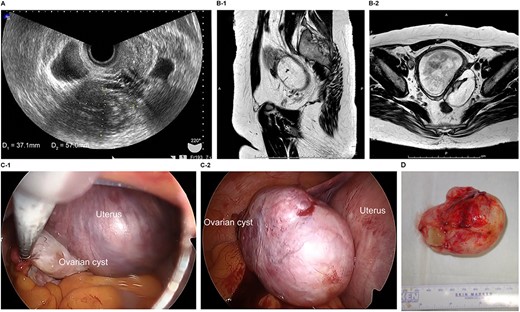

The patient was a 38-year-old, gravida 3, para 1 woman with no familial or medical history. She conceived naturally and was diagnosed at 7 weeks of gestation in another medical facility. She was subsequently referred to our hospital for further examination and operation. Transvaginal ultrasonography (TVUS) revealed a fetus in the uterus and a mass 7 cm in diameter on the right ovary. Magnetic resonance imaging (MRI) revealed right ovarian cystic tumors with fat tissue. The patient’s laboratory values, including levels of tumor markers (e.g. carcinoembryonic antigen, CEA; cancer antigen 125, CA 125; cancer antigen19–9, CA 19–9 and squamous cell carcinoma antigen, SCC), were within the normal limits. The tumor was diagnosed pre-operatively as a dermoid cyst. We performed single-port laparoscopic surgery at 16 weeks and 2 days gestation to remove the right ovarian cysts. The total procedure was performed within 55 minutes, and there were no complications (Fig. 1).

Imaging studies and laparoscopic views and specimen photograph of case 1. (A) Transvaginal ultrasound image showing an ovarian cyst. (B-1) Sagittal T2-weighted magnetic resonance image (MRI) showing an ovarian cyst. (B-2) Axial T2-weighted MRI showing an ovarian cyst. (C-1) Gestational uterus: ovarian cyst was moved from the pouch of Douglas. (C-2) Ovarian cyst was moved and located on the gestational uterus. (D) Ovarian Cyst.